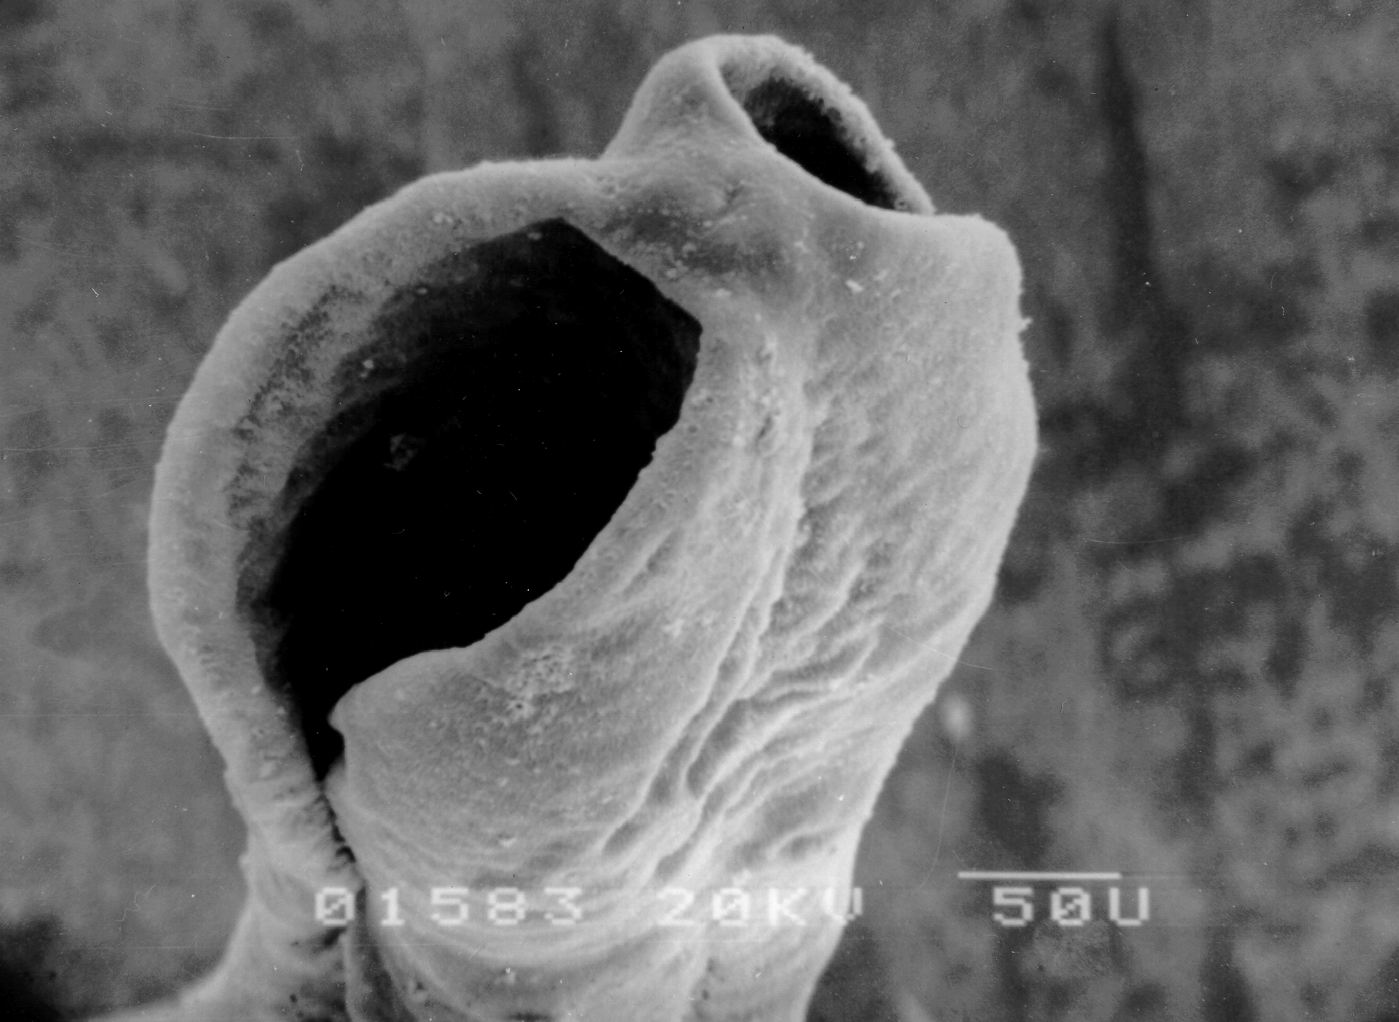

曼氏迭宫绦虫头节